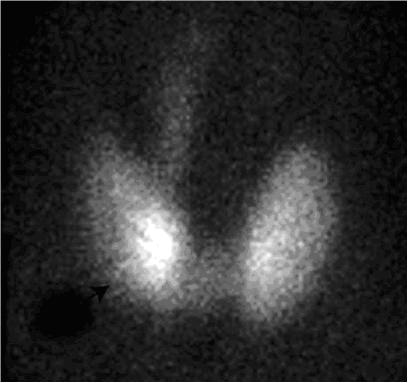

Prin detectarea la suprafaţă a radiaţiilor emise de radiotrasor, pot fi evaluate atât morfologia (dimensiuni, poziţie, forma) cât şi funcţia glandei tiroide (per ansamblu şi a eventualelor structuri nodulare). Astfel, se realizează evaluarea variantelor morfofuncţionale ale tiroidei normale: poziţia (tiroida situată retrosternală, latero-cervicală sau sublinguală), numărul lobilor tiroidieni (lob accesoriu, agenezie a unui lob tiroidian), forma glandei (ovală, de litera U sau V) şi eventualele asimetrii de captare a radiofarmaceuticului (fixare preferenţială la nivelul unui lob).

- evaluarea funcţiei unui nodul unic (necaptant-“rece”, hipercaptant “cald”, intens hipercaptant “fierbinte”);

- indicarea posibilei autonomii a funcţiei unui nodul «fierbinte» (nodul toxic Plummer);